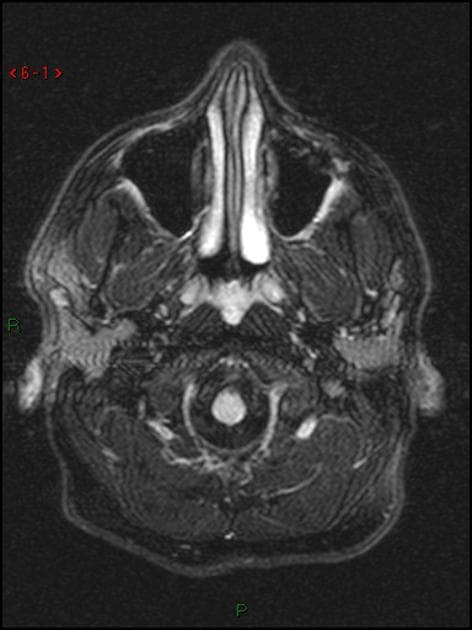

Axial T2

- Ghi nhận nhiều tổn thương kích thước thay đổi, ở hai bên tại vùng quanh não thất (periventricular), vùng cận vỏ (juxtacortical), vùng tiểu não, chi sau bên trái của bao trong (left posterior limb of the internal capsule) và cánh cầu bên trái (left brachium pontis).

- Các tổn thương vùng quanh não thất định hướng vuông góc với não thất (Dawson fingers).

- Các tổn thương biểu hiện tín hiệu giảm trên T1, tăng tín hiệu trên T2 và FLAIR.

- Một số tổn thương cho thấy hiện tượng T2 shine-through (tín hiệu tăng trên DWI và ADC tăng), trong khi một số khác, chủ yếu là các tổn thương quanh não thất, biểu hiện tín hiệu sáng dạng viền trên DWI với ADC ngoại vi giảm (hạn chế khuếch tán thật sự – true restriction).

- SWI phát hiện dấu hiệu tĩnh mạch trung tâm (central vein sign) tại tổn thương ở chi sau của bao trong (PLIC).